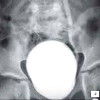

Детский цистограф. Радиоконтрастное исследование мочевого пузыря у детей. Ретроградная цистография у ребенка включает введение контрастного вещества, содержащего водорастворимый йод, через катетер в мочевой пузырь и серию рентгенограмм на уровне мочевого пузыря и после опорожнения. Во время исследования оцениваются форма и контуры мочевого пузыря, наличие дефектов наполнения и опорожнения. При использовании цистографии в детской урологии диагностируются дивертикулы мочевого пузыря, пузырно-мочеточниковый рефлюкс, свищи, камни и инородные тела, нейрогенный мочевой пузырь, разрыв мочевого пузыря и.

На нормальной цистограмме определяются четкие непрерывные контуры мочевого пузыря, их обычная емкость и уретровезикальный угол относительно независимых стенок. Уретра и мочеточники обычно не заполнены контрастом. Если данные цистографии неудовлетворительны или сомнительны, МРТ или МСКТ мочевого пузыря могут быть отнесены к ребенку. С полученными рентгенограммами и описанием изображений в будущем вам следует проконсультироваться с нефрологом или детским урологом.